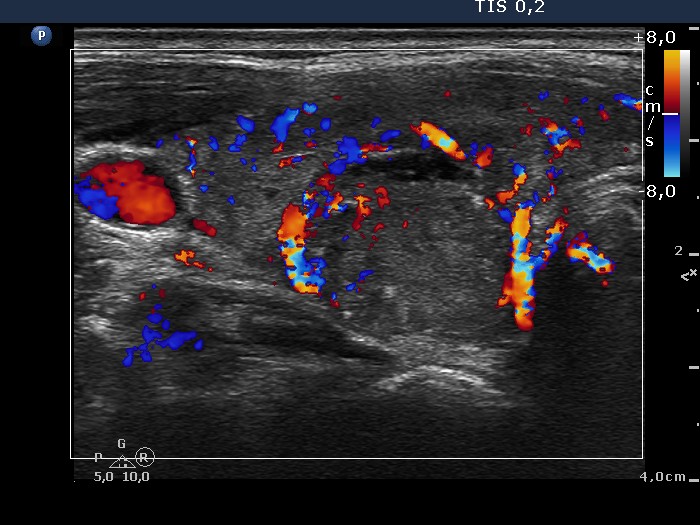

100 consecutive cases of papillary cancer - case 035

Present examination (ultrasonographic picture 6)

Lower part of the right lobe, transverse scan, color Doppler mode. The intralesional vascularization is less pronounced compared with the non-lesional part of the lobe.